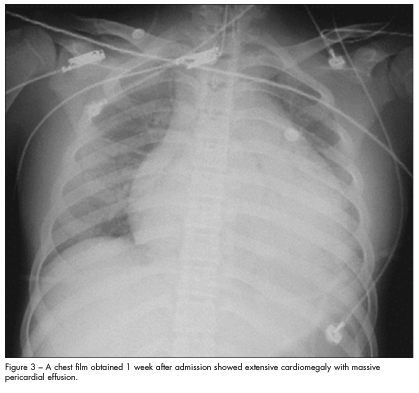

Heart failure from massive pericardial effusion was highly suspected. Treatment with high-dose intravenous corticosteroids was initiated; however, the dyspnea persisted and the patient’s symptoms worsened. A chest film obtained 1 week after admission showed extensive cardiomegaly with massive pericardial effusion (Figure 3). Extracorporeal membrane oxygenation therapy was started. The differential diagnosis of cardiomegaly with and without pericardial effusion in children was considered (Table).